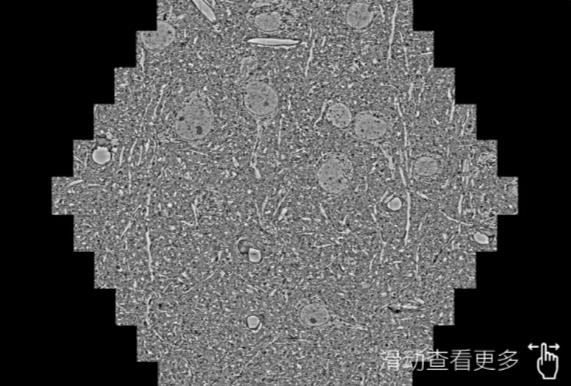

鼠脑切片。左图使用郑州蔡司郑州扫描电镜MultiSEM706对165μmx143pm面积区域成像,耗时仅需1.5秒。右图为鼠脑切片中30μm区域放大效果。样品由芝加哥大学B.Kasthuri提供。

使用蔡司高速郑州扫描电镜MultiSEM对1mm²人脑皮层组织进行高分辨成像,并对其中的各种细胞结构进行三维重构分析。左图展示了2x3mm²组织平面中锥体神经元的三维重构效果。右图显示了局部体积神经元三维重构。图像由哈佛大学chtman实验室提供,渲染图由D. Berger 制作。